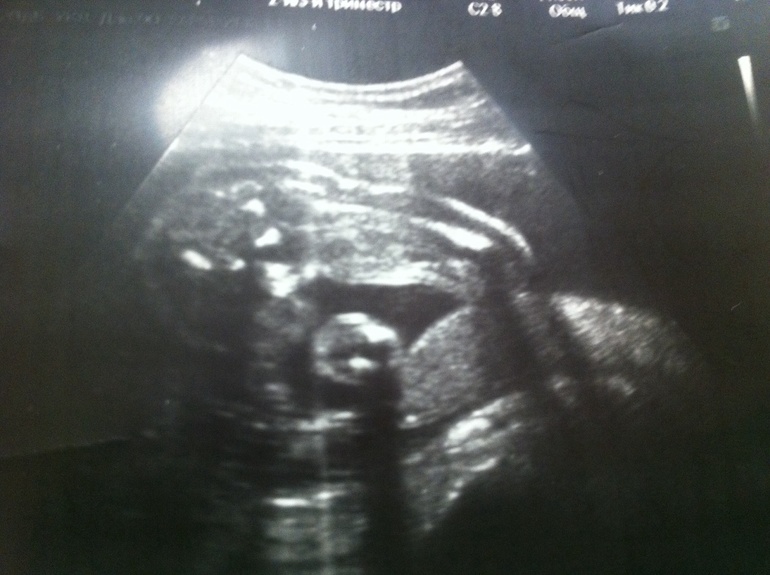

Может, кто по фото может все-таки что-то сказать? Первое фото - 24 неделя, где увидели девочку. 2 и 3 фото - 25 неделя, где увидели мальчика (врач маркером яички обвела). Пениса не видно, говорит, что это яички такие большие, половые губы такими не бывают... И тогда, и тогда говорят "100%". Ну смешно уже...

Тут сказали девочка: